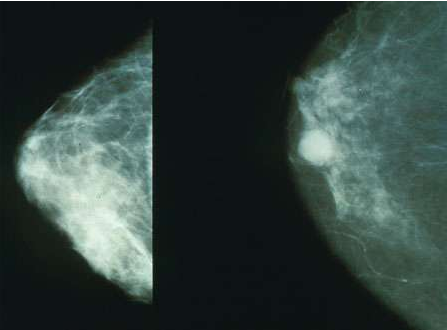

近日,一项刊登在国际杂志Theranostics上的研究报告中,来自乌普萨拉大学的研究人员通过研究开发了一种新型基于成像的方法,其可以帮助确定乳腺癌治疗方法是否同当前的标准化方法一样准确有效,同时还可以帮助减少侵入性组织抽样的需要;相关研究结果表明该方法或可帮助开发出针对不同个体的满意化治疗方法。

测定生长因子HER2(人类表皮生长因子受体2)可以作为一种重要的工具来确定乳腺癌治疗方法的准确性,而靶向作用HER2的治疗方法相当昂贵,但其可以挽救很多患者的寿命,然而一旦转移性的肿瘤不能够表达HER2那么靶向性的治疗方法或许就并没有什么效果,当前在转移性癌症中提高HER2表达的诊断方法是基于对外科手术或穿刺获取组织样本的检测。

研究者进行这项研究的目的在于开发一种简单非侵入性的技能,即基于机体全身的PET/CT成像技能,从而来将相同患者机体成像分析的结果同侵入性测定的结果进行对比。本文研究中研究者对16名正在进行转移性乳腺癌治疗方法治疗的患者进行研究,其中12名患者被诊断为HER2阳性的原发性肿瘤,而其他四名患者被诊断为HER2阴性患者,所有的患者都利用PET/CT结合新型的分子ABY-025亲合体来进行扫描,ABY-025亲合体可以利用放射性同位素镓-68进行标记。

研究结果表明,利用这种新方法可以准确测定转移性肿瘤中HER2表达的量,此外转移性肿瘤中HER2表达的量同原发性肿瘤中并不相同,这就造成了不同患者对治疗方法的表现不同;这种新型治疗方法可以替代侵入性的组织取样技能,研究者Jens Sorensen 说道,后期我们将计划在更多的医院中开展这项研究来证实利用这种新方法对患者带来的有益效应和帮助。